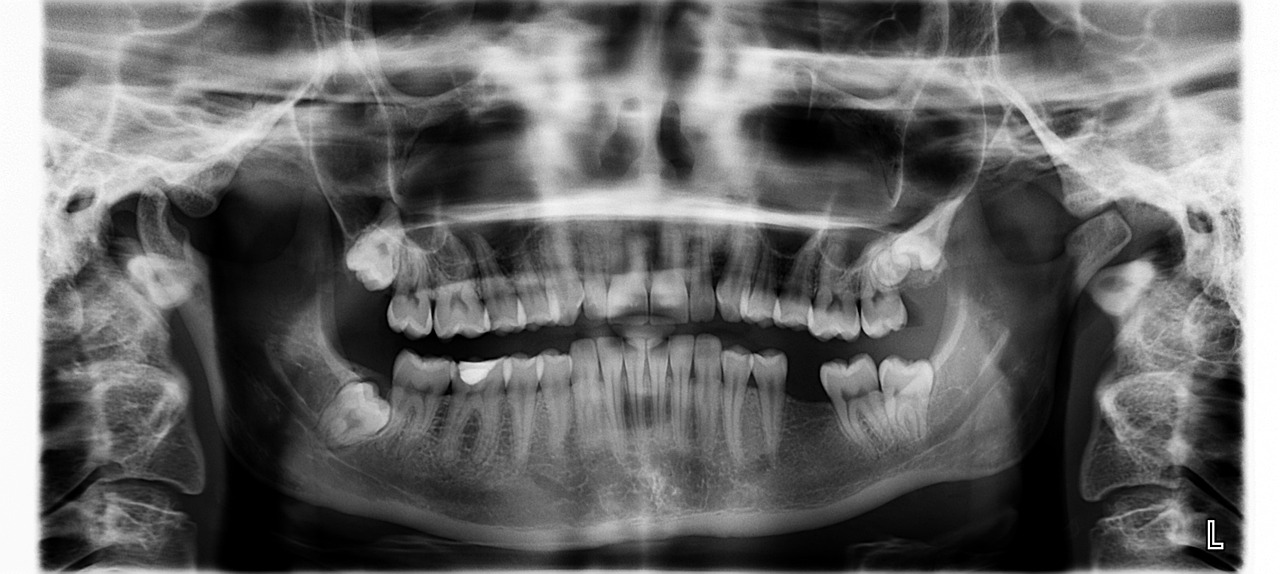

예방 관리는 치아 문제가 발생한 후 치료하는 것보다 훨씬 더 효과적이고 비용도 저렴합니다. 구강 건강을 소홀히 하면 충치, 구취, 치아 손실로 이어질 수 있으며, 이는 근관이나 임플란트와 같은 귀중한 치료법을 수반할 수 있습니다. 지금 좋은 치아 위생 관행을 장려함으로써 미소를 위한 더 건강한 미래에 투자하는 것입니다.